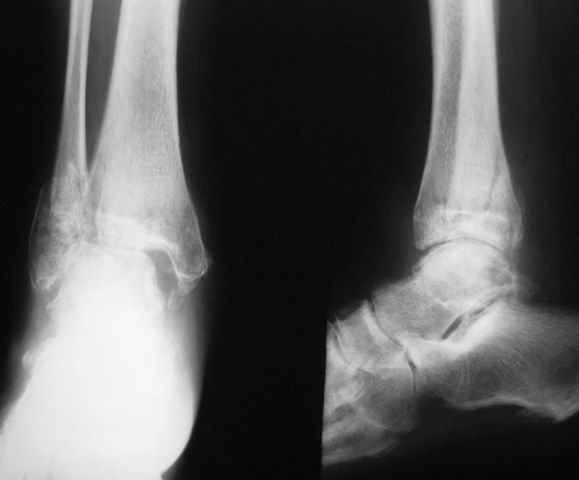

На фоне свищевой формы остеомиелита (скорее всего, речь идет об этом) о любой одноэтапной реконструктивной операции думать сложно. Если же все-таки решаться на одноэтапную операцию, то только убедившись, что гнойный процесс ограничивается внутренней лодыжкой. В этом случае возможен артродез с резекцией лодыжек (как на представленной рентгенограмме). Подобная операция позволяет относительно легко установить кости в оптимальное для артродеза положение, а также устранить гнойный очаг.

При поступлении произведено вправление вывиха, трансартикулярная фиксация голеностопного сустава спицами и ПХО раны.

Что касается существа дела, согласен, ждать здесь нечего, только артродез. Но есть нюансы. После удаления хряща поверхности тарана и большеберцовой кости неконгруэнтны, мы широким долотом формируем плоские поверхности на контактирующих участках, конечно, при этом теряем около 1,5-2 см длины конечности, зато уж контакт так контакт.